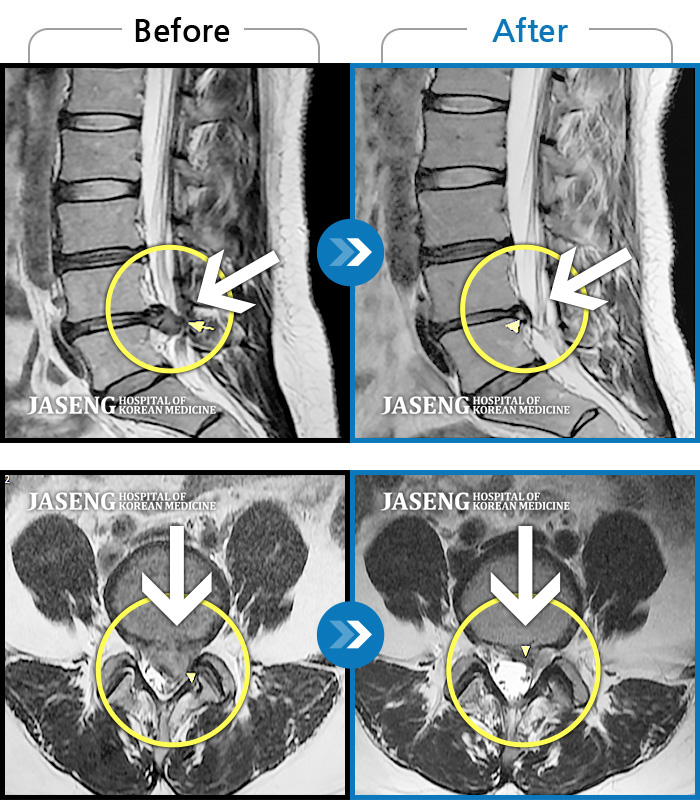

허리디스크

해운대 · 김상돈 원장

아래쪽 허리와 우측 골반에 통증이 있었습니다.

촬영시기

2019.08.26 ~ 2025.08.09

2025.08.14

조회수 262